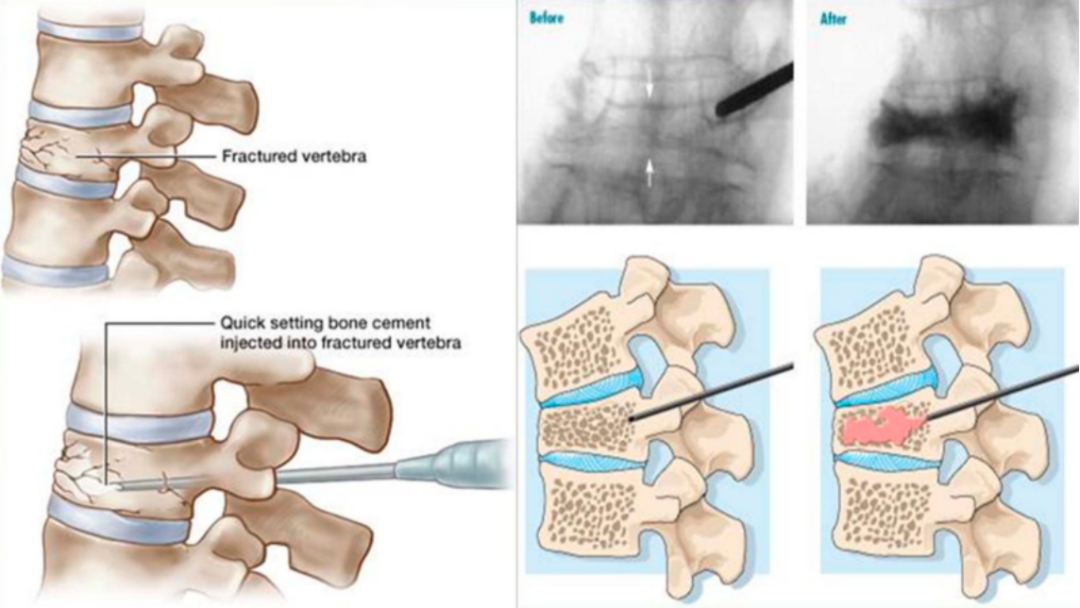

椎体强化手术,包括椎体成形术(PVP)和经皮球囊扩张椎体后凸成形术(PKP),是目前最常用的微创手术治疗方法。通过经皮向骨折椎体注射骨水泥,能够迅速缓解疼痛,增强病椎的强度和刚度,防止椎体进一步塌陷和畸形,而且没有传统开放手术内固定带来的手术创伤以及远期可能出现的内固定失败。PKP还可通过球囊扩张使压缩骨折得到一定程度的复位,球囊取出后在椎体内形成的空腔有利于骨水泥低压力注入,有效降低骨水泥渗漏率。

椎体成形术(PVP):

经皮椎体成形术(percutaneous vertebroplasty,PVP)是经皮由椎弓根置入,骨水泥注入椎体,从力学上增强其结构强度。

经皮球囊扩张椎体后凸成形术(PKP)

①正位、侧位影像监测下,经皮由椎弓根置入;

②置入导管球囊扩张,向气囊内充气扩张,以恢复椎体高度;

③放出气囊内气体,移走气囊,注入骨水泥维持矫正后形态